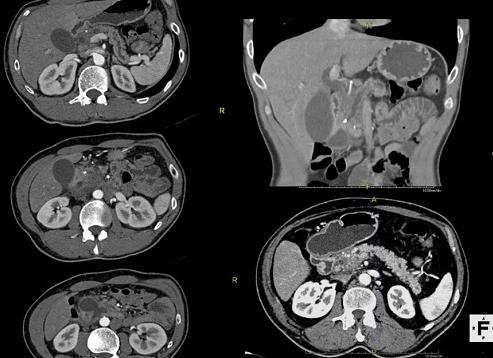

КТ брюшной полости назначают при подозрении на наличие воспалительных или опухолевых процессов в органах пищеварительного тракта, мочевыделительной системы, забрюшинного пространства и малого таза. В зависимости от целей исследования, компьютерная томография может проводиться с контрастным усилением или без него.

Подготовка к КТ брюшной полости

Компьютерная томография требуется, когда есть подозрения на заболевания в забрюшинном пространстве, мочевыделительной и репродуктивной системах, пищеварительном тракте. Компьютерная диагностика (КТ) осуществляется при помощи рентгеновских лучей. Для точного результата обследования надо провести качественную подготовку к КТ брюшной полости.

Подробнее о процедуре компьютерной томографии

Во время обследования сканируются все внутренние органы, также лимфатические узлы и сосуды. Необходимая область фиксируется в 3 разных плоскостях, это дает наиболее точную картину состояния брюшной и забрюшинной областей. Протоколы исследований при КТ могут включать различные органы, не только находящиеся в брюшной полости.

Процедура КТ (РКТ) – безболезненна, ее проводят с контрастированием или без него. Обследование проводится при лежачем положении пациента. Важным моментом для проведения компьютерной томографии является подготовка к ней в виде диет, иногда приема лекарств.

Что показывает КТ

С помощью КТ исследуются проблемы органов забрюшинного пространства, выявляют:

В каких органах проверяют наличие патологий?

Анализ КТ может выявить аномальные изменения в:

При исследовании брюшной полости просвечиваются внутренности и их состояние, изображение поступает на компьютер. Если требуются более четкие данные, тогда назначают КТ определённого органа с использованием контраста. Нативный способ томографии делается без контрастирования.